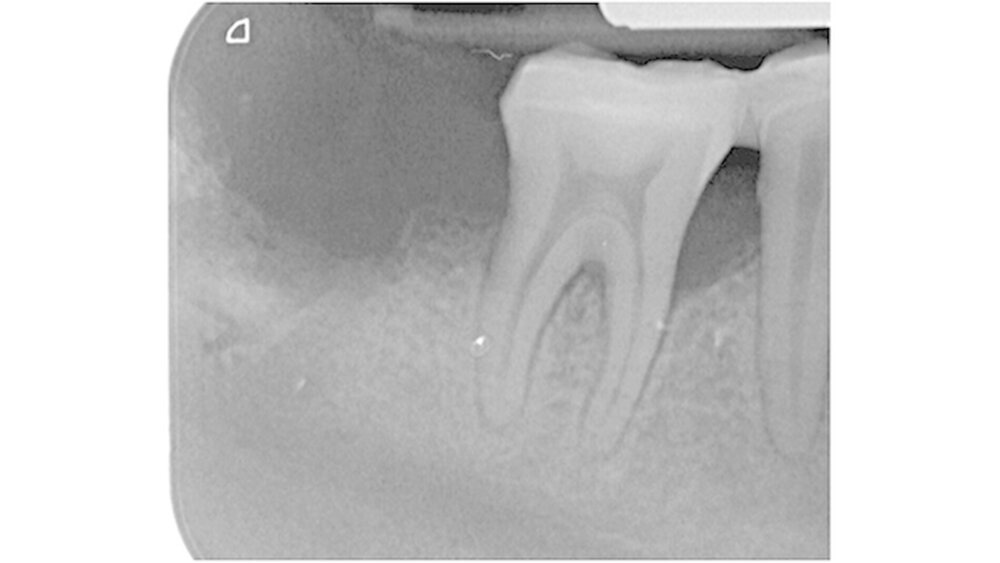

Eine 34-jährige Patientin stellte sich zur Wurzelkanalbehandlung des Zahns 47 und zur Behandlung ihrer generalisierten schweren chronischen Parodontitis in der Poliklinik für Zahnerhaltung und Parodontologie der Universitätsmedizin Rostock vor. Nach Trepanation und manueller Aufbereitung des infizierten Wurzelkanals im Studentenkurs wurde eine Röntgen-Messaufnahme mit einem Guttaperchapoint in der Größe des zuletzt verwendeten Instruments angefertigt.

Die Aufnahme zeigte diesen Guttaperchapoint zwei Millimeter über den röntgenologischen Apex herausragen (Abbildung 1). Der Stift wurde wieder entfernt, eine Zwischeneinlage mit Calciumhydroxid appliziert und der Zahn temporär mit Glasionomerzement verschlossen. Die Patientin verließ die Klinik beschwerdefrei.